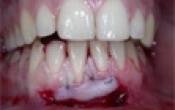

Double greffe gingivale libre sur les 2 canines mandibulaires en vue d'un traitement orthodontique